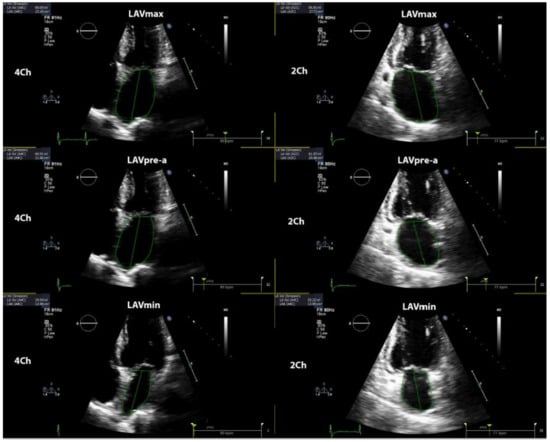

LA phasic function was determined by volumetric and strain analysis. LA volumes were obtained in three various parts of the cardiac cycle: maximal LA volume was calculated just before the mitral valve opening, pre-A (pre atrial contraction) LA volume was evaluated at the beginning of atrial systole (peak of P wave in ECG), and minimal LA volume was assessed at the mitral valve closure. All LA volumes were determined according to the biplane method in four- and two-chamber views and all the values were indexed for BSA. The total emptying volume (LA reservoir function parameter) was calculated as the difference between maximum and minimum LA volume; passive emptying volume (LA conduit function parameter) was computed as the difference between maximum and pre-A LA volume; and active emptying volume (LA booster function parameter) was calculated as the difference between pre-A and minimum LA volume [13]. Figure 1 shows the methodology of determination of LA volumes in the current study. Total emptying fraction (EF) was calculated as the ratio between total emptying volume and maximum LA volume; passive EF was computed as the ratio between passive and maximum; and active EF was evaluated as the proportion between active and pre-A LA volume.

Figure 1. Shows the methodology of determination of left atrial volumes. LAVmax—maximal left atrial volume; LAVmin—minimal left atrial volume; LAVpre-a—left atrial volume before atrial contraction.